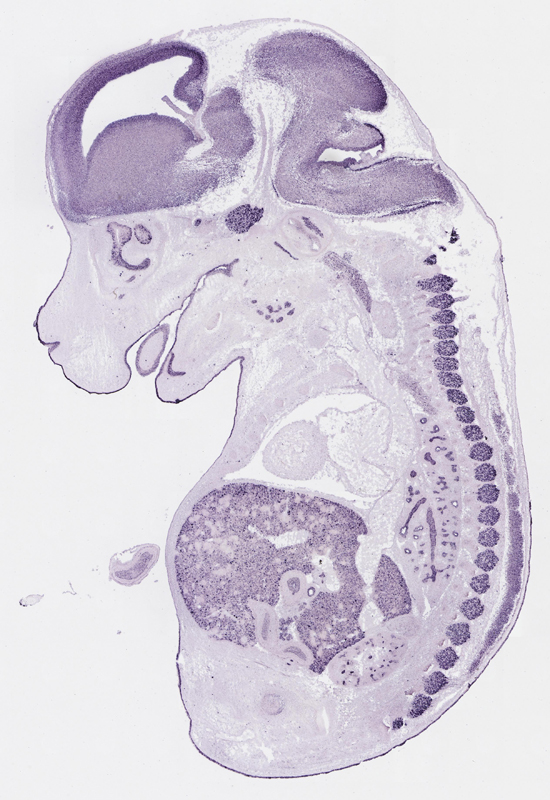

Specimen

euxassay_003287_04:

embryonic day 14.5